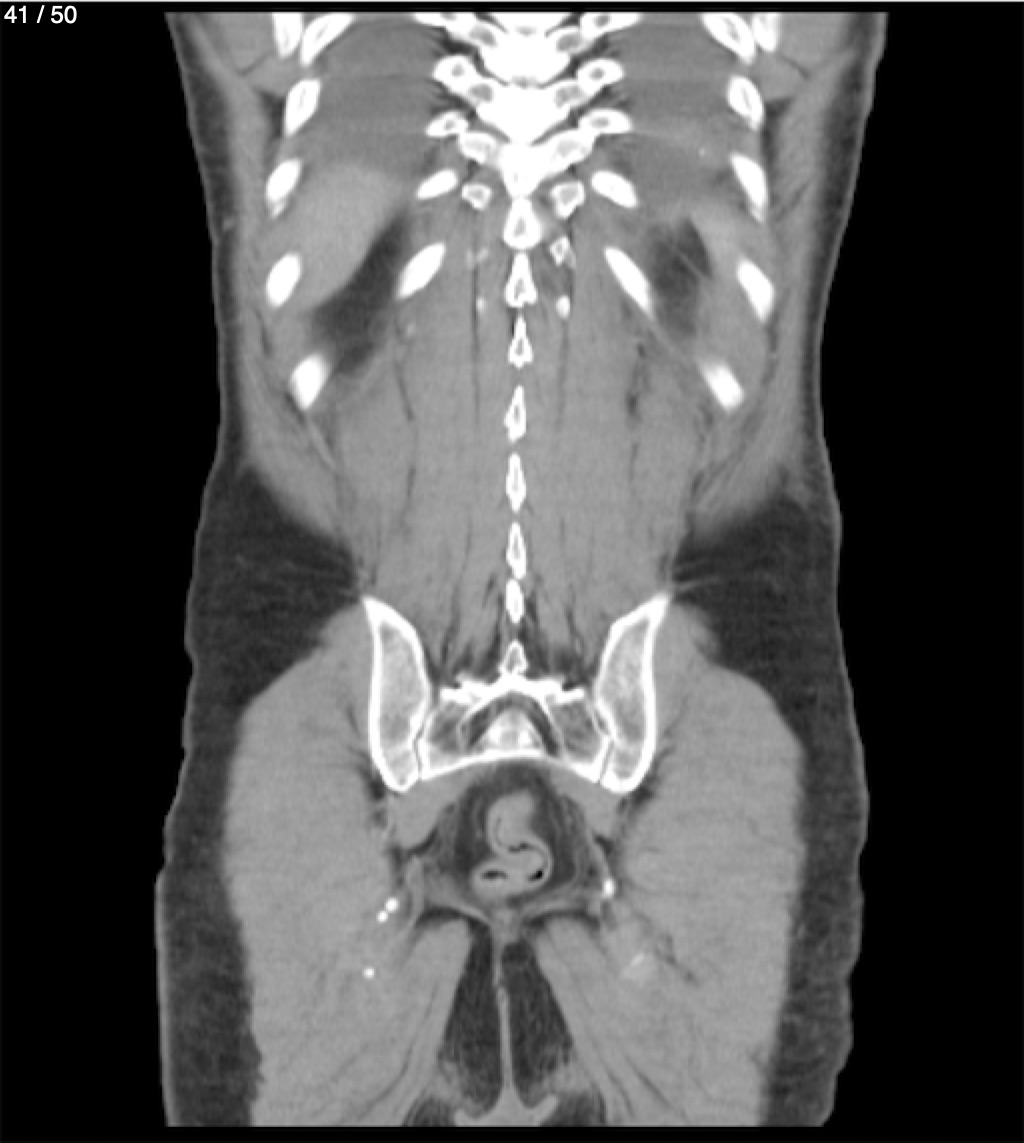

Alonso Victorio Ruiz 62A - T.C Abdomen Syc